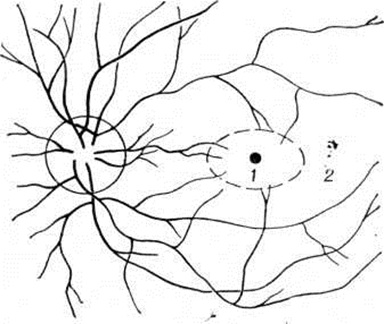

Зрительную фиксацию исследуют (при выключенном втором глазе) при помощи офтальмоскопов, в систему которых введён фиксационный объект. При правильной фиксации объект проецируется на центральную ямку, при неправильной — на парацентральные участки сетчатки (рисунок 3).